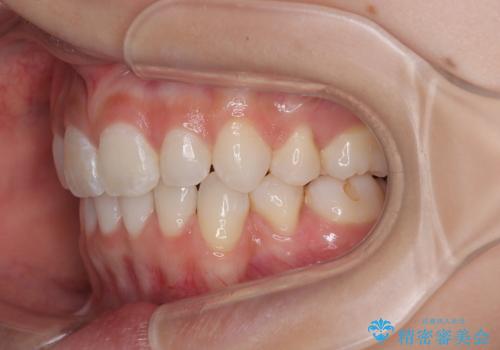

下唇に前歯が当たって跡が残ってしまう状態でしたが、スッキリとした口元に仕上げることができました。

- 口を閉じたときに飛び出してしまう上顎前歯を気にして来院された患者様です。

下顎はデコボコが気になっていたため、上下左右第一小臼歯4本を抜去して、ワイヤー装置にて口元の突出感を改善するよう矯正治療を行うこととしました。